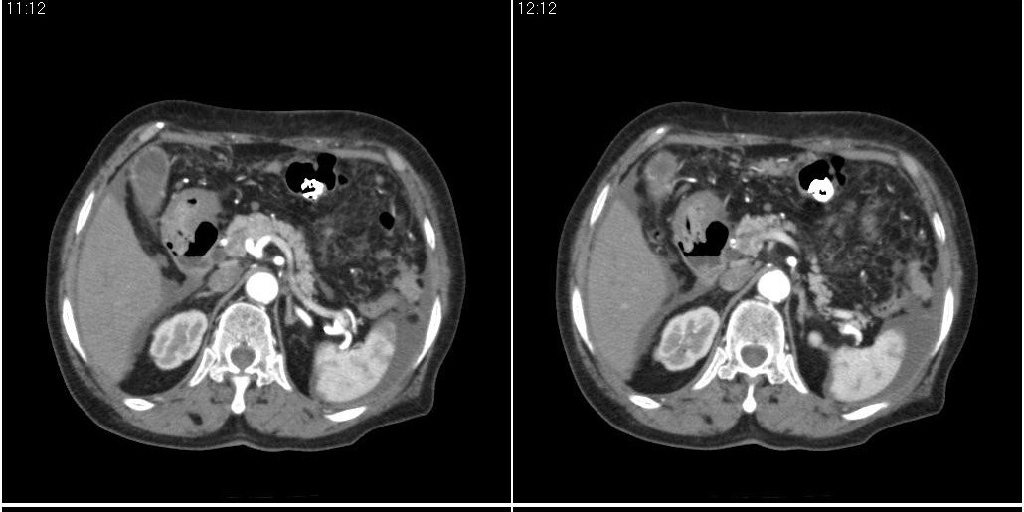

胆囊有问题么,是结石么?胆囊内异常密度平扫30hu左右,增强各期无变化。

胆囊内稍高密度影,无强化,胆囊壁增厚,周围见低密度影,右侧膈肌角及脾周水样密度,支持胆囊泥沙样结石,胆囊炎、胆囊窝积液,胸腹水。